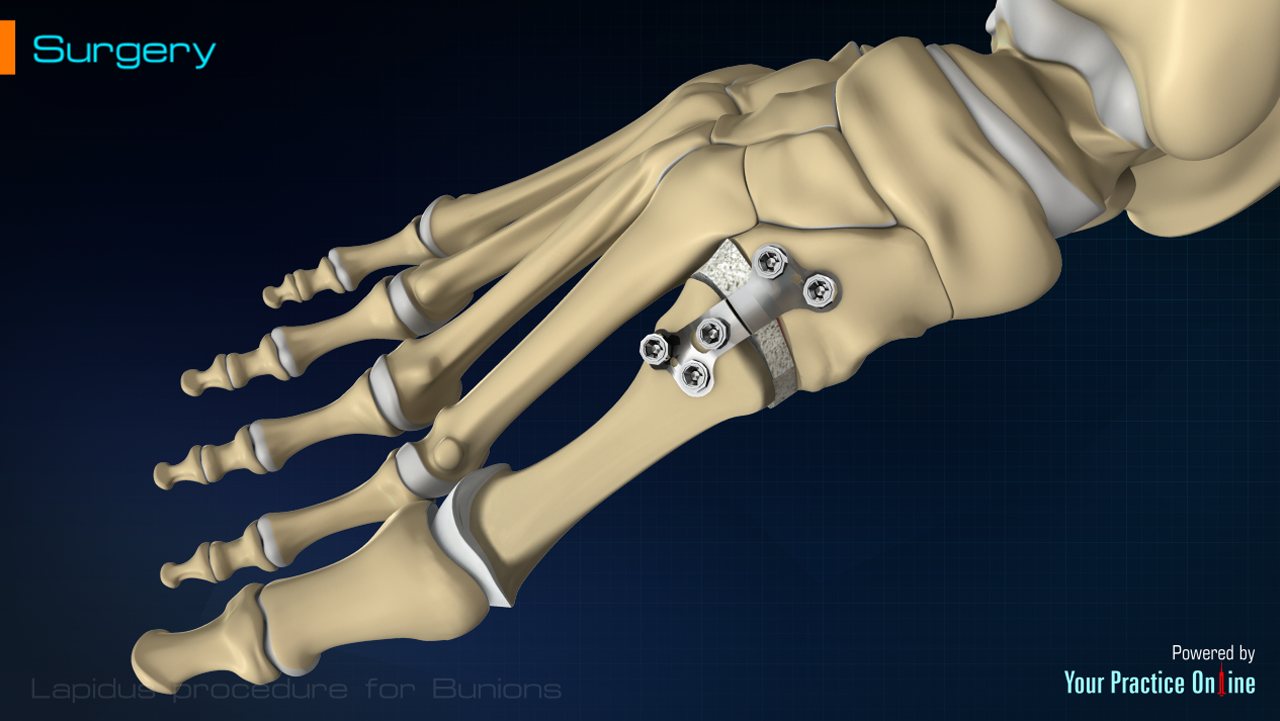

Медицинские решения: Операция по коррекции Hallux valgus

Раздел: Галерея впечатлений